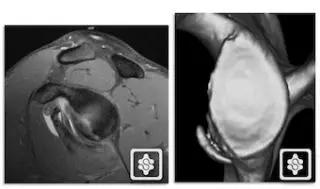

3. 骨性 Bankart 损伤(Bony Bankart lesion)

下盂肱韧带盂唇复合体损伤同时伴有关节盂前下方的撕脱性骨折。由于关节盂前下方的骨质缺损,可以导致梨形的肩盂变为「倒梨形」结构,出现关节不稳的主要因素。

骨性 Bankart 损伤的 MR(左)和 CT(右)(来源:ShoulderDoc)